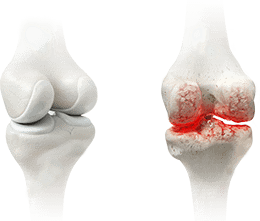

9.22% Sportivii sunt cei mai frecvenți clienți ai sălilor de recuperare fizică terapeutică și de fizioterapie. Ei prezintă leziuni cu diferite grade de severitate care pot fi împărțite în două grupuri: leziuni musculare și leziuni articulare. Rupturi, întinderi, artroză cronică. Nu poți evita riscurile dacă nu te protejezi la timp.